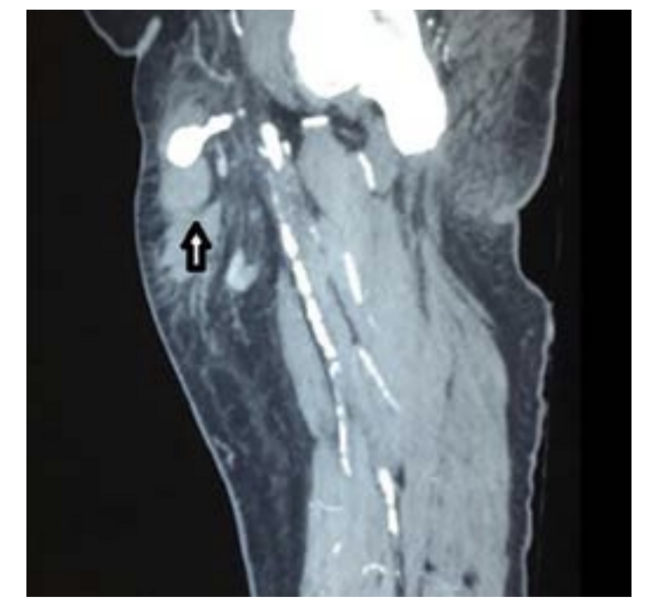

On the ultrasound arterial doppler a heterogeneously hyperechoic area was found at the upper part of the right thigh, with skin discoloration suggestive of a hematoma. This had a well-defined echogenic area with a Ying and Yang color flow, and swirling suggestive of a pseudoaneurysm. This appeared to arise from the common femoral artery (Figure 1). Since the swelling was very large, to enable further treatment decisions we sent the patient for a CT angiography of the thigh (Figures 2-5).

CT Angiogram Findings

A pseudoaneurysm arising from anterior aspect of the right common femoral artery (CFA) just above bifurcation was observed with a sac noted in the subcutaneous space that measured 1.9 x 1.4 cm. A tract from this sac had a length of 2.6 cm and arose from the CFA. A hematoma was noted in the anterior and medial aspect of the thigh in the subcutaneous space adjacent to the pseudoaneurysm (Figures 2-5).